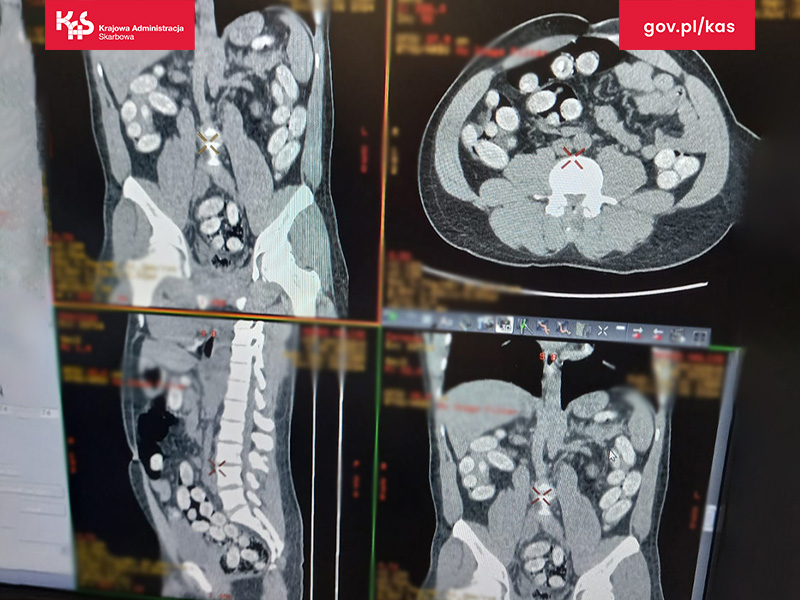

Prześwietlenie - widoczne kapsułki w organizmie zatrzymanego

Mężczyznę przewieziono do szpitala. Wyniki tomografii komputerowej przewodu pokarmowego potwierdziły wewnątrzustrojowy przemyt środków odurzających.

Podróżny w swoim organizmie przemycał w kapsułkach prawie 1,2 kg narkotyków.